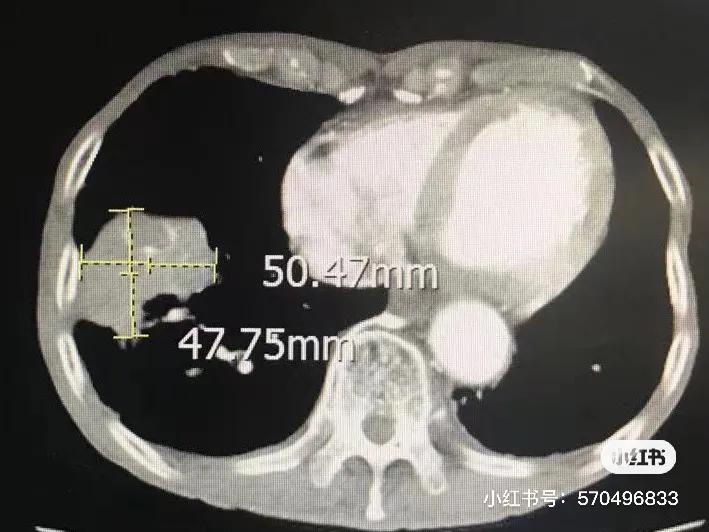

第一次冷冻后一个月CT